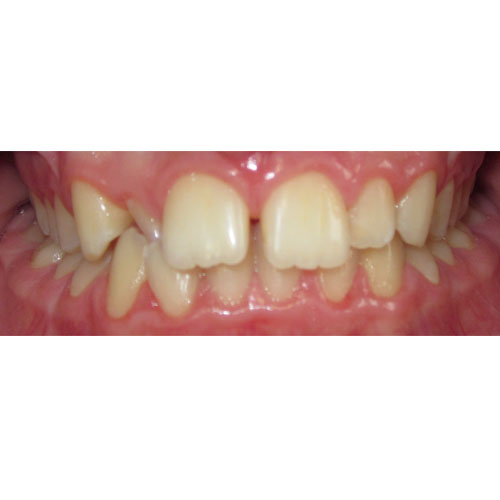

Nasze rezultaty